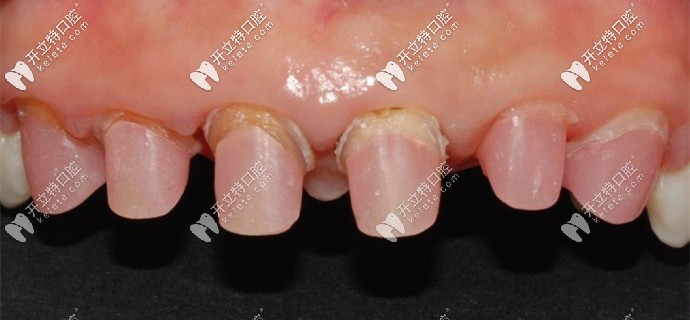

被磨掉1/2的基牙

牙醫(yī)說(shuō)我的牙齒情況不容樂(lè)觀,之前醫(yī)生操作不當(dāng)?shù)脑颍瑢?dǎo)致牙槽骨萎縮、基牙腐爛,只能建議拔掉做種植牙。

我的基牙已經(jīng)腐爛了只能做種植牙